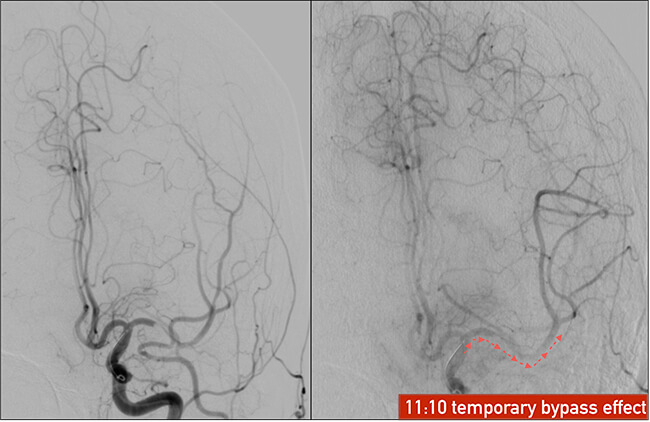

Περιμένουμε 5 λεπτά ώστε το πλέγμα του stent-retriever να βυθιστεί μέσα στον θρόμβο και το stent-retriever να αλληλεπιδράσει και να εκπτυχθεί σε όλο το μήκος του θρόμβου. Στην διάρκεια αυτή κάνουμε μία έγχυση από τον οδηγό καθετήρα γιά δούμε εάν έχει αποκατασταθεί η ροή μέσα στο αποφραγμένο αγγείο. Αυτό συμβαίνει όταν ο θρόμβος έχει απωθηθεί από το stent-retriever και έχει δημιουργηθεί βατός αυλός κατά μήκος της αποφράξεως.

Όταν δούμε αυτή την εικόνα της πρώτης επανασηραγγοποίησης, αυτό είναι καλό προγνωστικό σημείο γιά την συνέχεια και αποτελεί ένδειξη γιά επιτυχή αφαίρεση του θρόμβου στην συνέχεια.